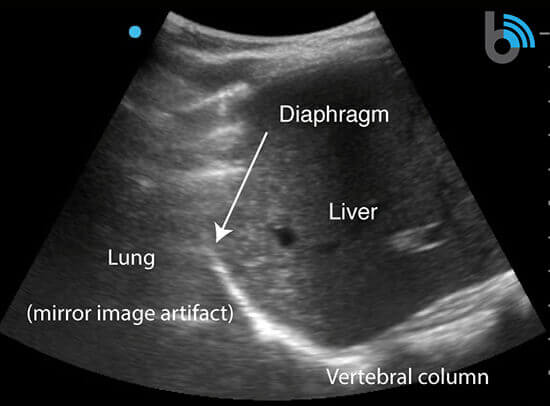

- A normal exam will reveal the liver/spleen, diaphragm, mirror image of the liver/spleen superior to the diaphragm, and the vertebral column lying posterior to the liver/spine (“spine sign”).

- The lung cannot be visualized due to the large acoustic impedance between the chest wall and air filled alveoli.

- The spine sign is only present posterior to the liver/spleen where ultrasound waves can pass through the structures to reach the vertebral column.

- The spine sign will not be present superior to the diaphragm, as the ultrasound waves are not transmitted through a normal aerated lung.